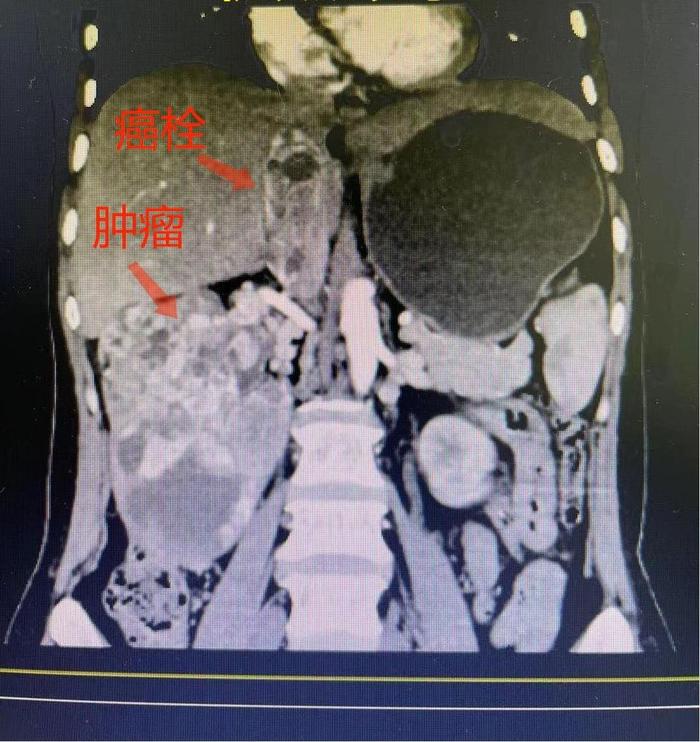

8月的一天中午,在大多数人午饭时间,复旦大学附属肿瘤医院浦东院区78号手术室内却异常紧张而又忙碌。十余位顶尖医务工作者都在紧锣密鼓的准备着一场“硬仗”。这是由泌尿男生殖系统肿瘤首席专家叶定伟教授领衔,泌尿外科张海梁、曹达龙教授担纲,麻醉科孙教授、顾教授等保驾护航,护理部顾老师、石老师等精准辅助的一台超高难度右肾癌根治性切除+下腔静脉III级癌栓取出术。这一“突破禁区”的手术的顺利完成,彰显了复旦大学附属肿瘤医院泌尿外科肾癌诊室团队应对肾癌伴高位腔静脉癌栓的“回天有术”,也给患者带来了根治肿瘤的希望。

该患者是一位中年女性,正值壮年。早在今年2月份,患者因“右侧腰部胀痛”于外院体检查出右侧肾脏长了一个12*8cm的巨大肿瘤,更严重的是患者还伴有右肾静脉、下腔静脉癌栓,腔静脉癌栓最高处已到达膈肌水平,已达到了传统观念下的“手术禁区”!患者突患大病,四处求医,然而均被告知病情棘手无法手术切除,生存时间不久。后患者抱着最后一丝希望,在病友的介绍下于2021年3月1日踏进了叶定伟教授的诊室。叶定伟教授对患者进行了详细的问诊与检查,并仔细阅片后,联合复旦大学附属肿瘤医院泌尿肿瘤多学科团队(MDT)之力,建议患者先行肾脏肿瘤穿刺明确病理,再针对性的进行靶向治疗,最后把握机会进行手术治疗。叶教授的一番话也让病人求医近一个月来首次见到了曙光。患者随即住院进行了穿刺,明确了病理类型为肾透明细胞癌,接着开始靶向治疗。当患者于2021年7月20日再次踏入叶教授诊室复查时,下腔静脉癌栓已显著退缩,患者终于搏得了手术切除肿瘤并取出癌栓的机会,对外科医生的真正挑战也正式开始了!叶定伟教授、张海梁教授和曹达龙教授会同麻醉科、护理部等多次讨论确定了手术方案。最终,团队仅用时2个多小时即完成了肾脏肿瘤的完整切除和下腔静脉癌栓的完整取出。当叶教授给患者家属看标本,描述术中情况,宣布手术非常成功的一刹那,患者家属的感激之情溢于言表。患者恢复良好,在术后第三天即可自己下床活动,术后第五天顺利出院。“你们团队不但能做别人不敢做、不能做的,还能做的那么好,真的太厉害了!真的是我们家的恩人!”患者家属质朴的言语是对复旦大学附属肿瘤医院叶定伟教授团队的最大肯定。也唯有数十年如一日的磨练技艺,不断突破,才能hold住手术台上那惊心动魄的2小时,给患者全新的生命重启。